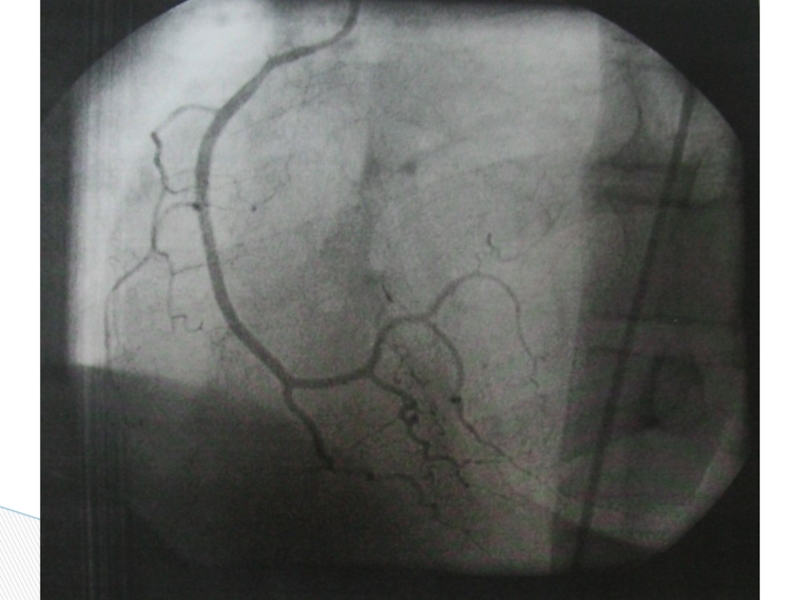

Слайд 39 Коронароангиография позволяет определить степень поражения коронарных артерий и провести ЧКВ:

Коронароангиография позволяет определить степень поражения коронарных артерий и провести ЧКВ:	стентирование	баллонирование